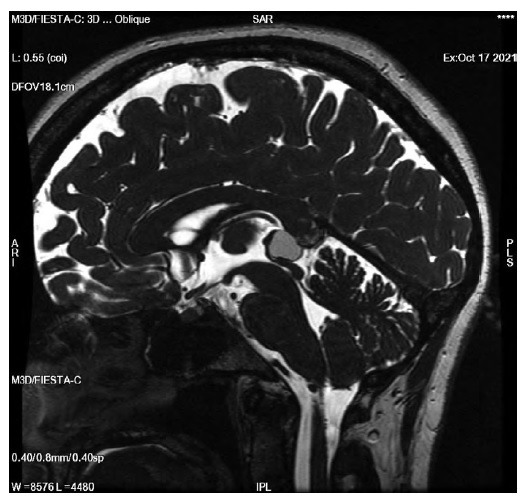

Одиночная однокамерная киста содержит гладкие стенки и жидкость, которая в 90% случаев имеет изоинтенсивный сигнал на МРТ по отношению к ликвору [32]. В10% случаев сигнал изоинтенсивный или слегка гиперинтенсивный относительно ликвора на импульсных последовательностяхТ2, Т2 FLAIR, FIESTA, что связано с повышенным содержанием белка (рис. 3).

Рис. 3. МРТ головного мозга, импульсная последовательность FIESTA. Срединный сагиттальный срез. Киста эпифиза размером более 10 мм, содержимое кистыс примесью белка. / Fig. 3. Brain MRI, FIESTA sequence. Midline sagittal section. Pineal cyst over 10 mm in size, the cyst contains a protein mixture.

Такой тип требует дифференциальной диагностики с атипичными кистозными образованиями, опухолями зародышевых клеток и паренхиматозными опухолями эпифиза [14].